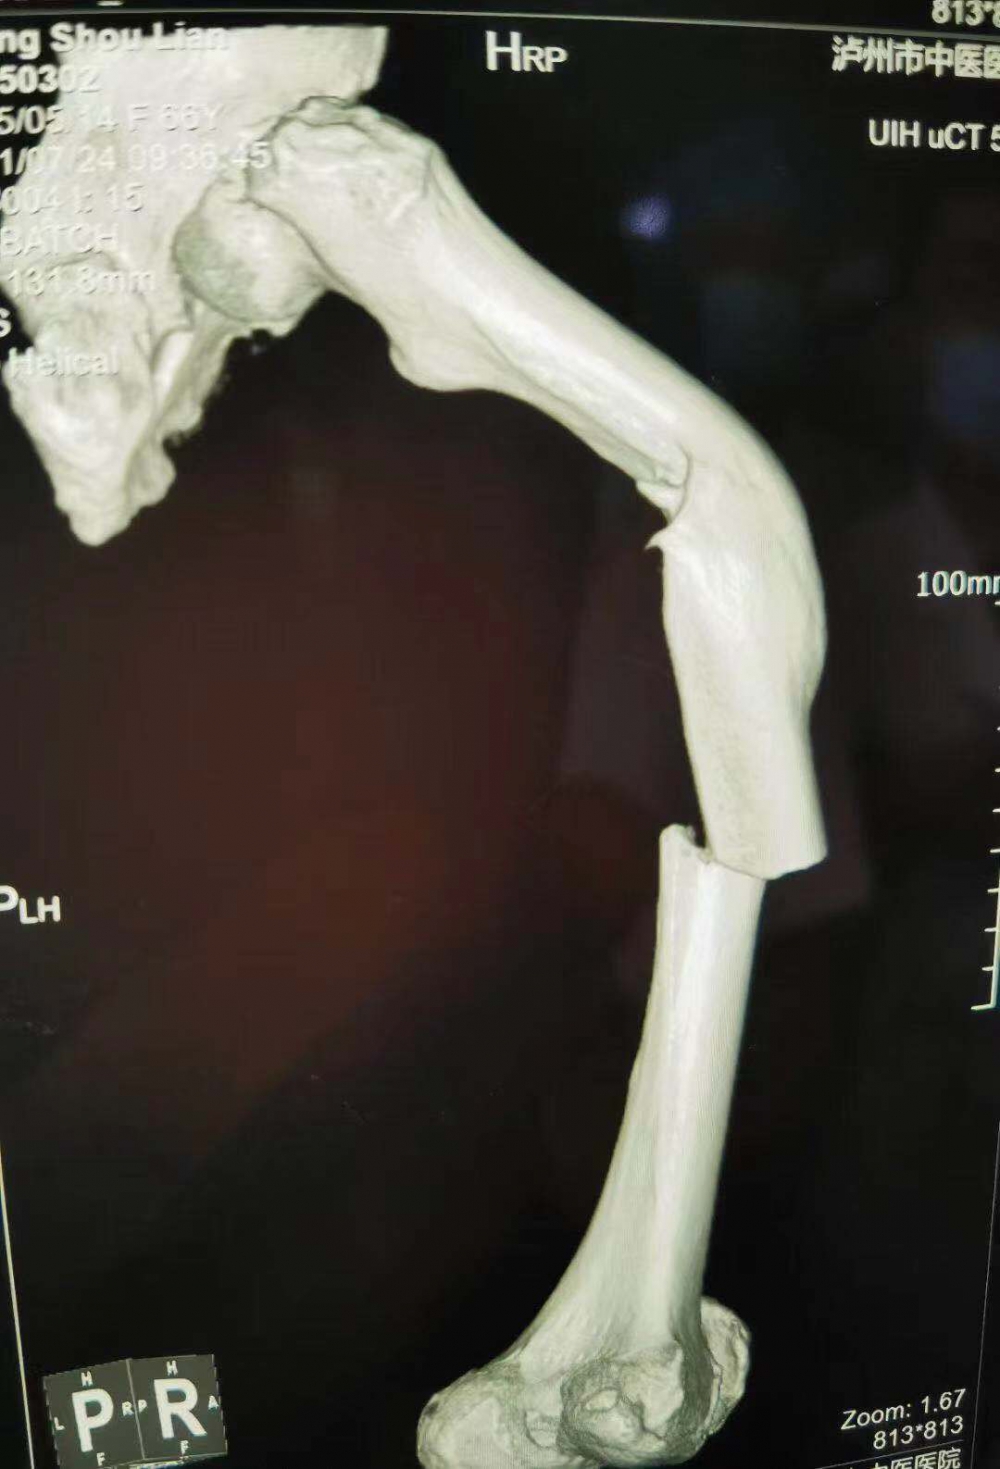

(股骨中段斷裂,上端有明顯畸形)

當她的X光片出來時,收治的醫(yī)生都被她的傷情嚇了一跳。原來此次她骨折的上端還有一處骨傷畸形愈合。這是什么情況呢?

原來張守蓮在三年前還摔傷過一次,當時在一家醫(yī)院進行了手法復位,但因操作不當,沒能復位成功,留下了后遺癥。三年來她都是以拄拐行走。